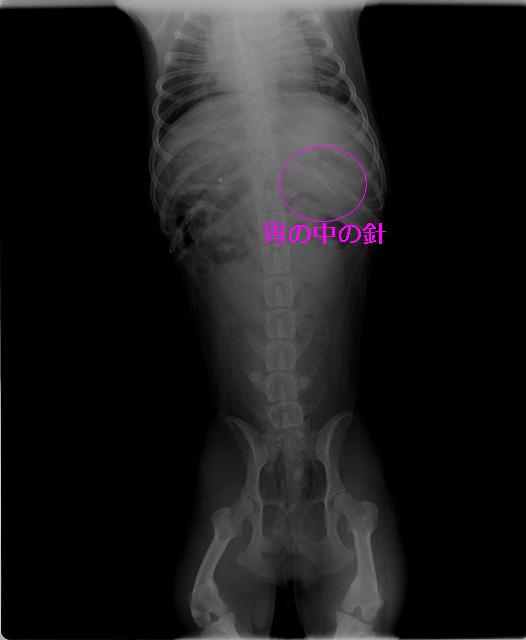

「ぬいぐるみを作っていたのですが、この時に使っていた針を飲み込んだかもしれません!」と言う事であるワンちゃんがいらっしゃいました。すぐにレントゲンを撮っておなかの中を調べてみると・・・

Img6576.jpg

Img6577.jpg

胃の中の針はすぐに見つけ出すことが出来ましたが、他にも何か胃の中にあるようです。